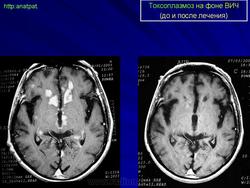

Токсоплазмоз у ВИЧ - инфицированных

Церебральный токсоплазмоз

Токсоплазмоз

Neurotoxoplasmosis

Дифференциальная диагностика изображения